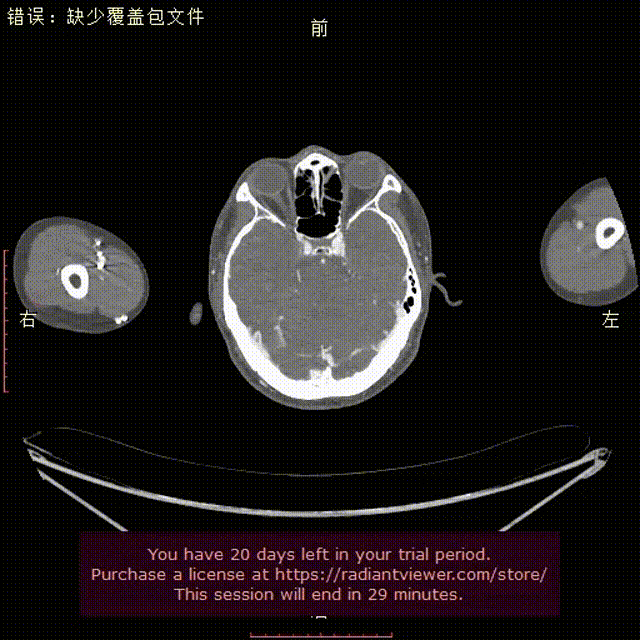

术前CTA提示右弓右降、合并Kommerell憩室,弓上各分支镜像分布。测量如下:

右弓右降,弓型陡峭,角度在40°左右

Kommerell憩室,38mm*30mm

考虑患者意愿,最后选择腔内手术方案。因该患者弓型陡峭,小弯侧锚定区较短,仅4.6mm,因此选择34mm直径、长度150mm支架,并考虑: